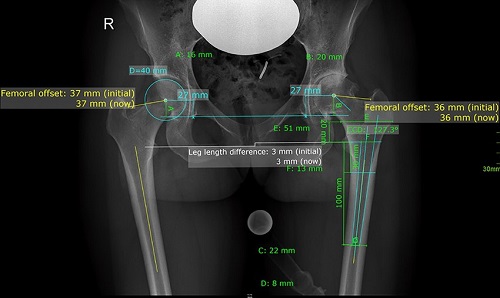

Trong phẫu thuật thay khớp háng toàn bộ, offset cần được tính toán trước phẫu thuật để có phương án phẫu thuật tốt nhất.

Có thể xác định offset trước phẫu thuật bằng đo đạc trên phim X quang thường quy tuy nhiên sẽ chính xác hơn nhiều nếu bác sĩ sử dụng phần mềm phẫu thuật Medicad HIP có đo đạc tự động.

3. Xác định độ bù chiều dài của chân trước và sau phẫu thuật và hiển thị trực quan bằng hình ảnh.

5. Xác định chênh lệch offset của xương đùi hai bên

Các thuật toán đo lường mới với sự hỗ trợ của máy tính đã được thiết lập để hỗ trợ bác sĩ phẫu thuật trong quá trình thay toàn bộ khớp trong mổ. Bác sĩ có thể đánh giá chiều dài chân và độ lệch được đo bằng hệ thống định vị đáng tin cậy trong quá trình tạo hình khớp háng .

Ước tính đền bù xương đùi. Độ di lệch xương đùi được định nghĩa là khoảng cách giữa trục dọc ở giữa của xương đùi đến tâm xoay của khớp háng.

6. Xác định chênh lệch offset của ổ cối hai bên

Mức độ chính xác của cỡ số ổ cối theo tỷ lệ phóng đại X quang từng trường hợp . Đánh giá mức độ chính xác của cỡ số ổ cối theo tỷ lệ phóng đại trung bình. Khoảng chênh lệch từ tâm xoay đến đường thẳng đứng đi qua góc dưới xương ổ cối cùng bên so với bên lành.